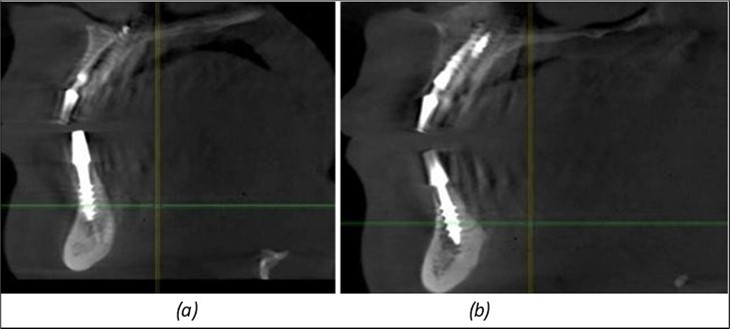

Figure 11.Implants in the anterior area anchored in the nasal cortex (BCS and TPG): (a), (c) – BCS implants fixed in the nasal cortex; (b), (d) – TPG implants fixed in the second nasal cortex with compression in the trabecular area.

Journal of Dentistry and Oral Implants - Periimplantitis

Figure 12.Implants fixed distally in quadrant 4 with fixation at the level of the mylohyoid line: (a) The most distal implant fixed in unaffected bone from the previous restoration; (b) The implant fixed in the area where the two stage implant was removed.